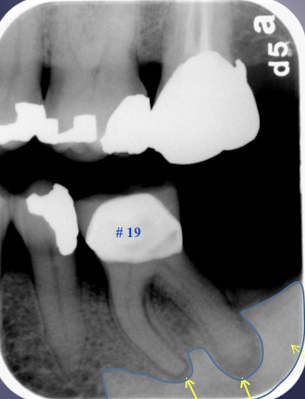

in maxillary M lift floor of max sinus!

what are some effects of periapical inflammatory disease on surrounding structures?

bone deposition

alteration in trabecular bone pattern and marrow spaces

periosteal new bone formation

perforation of bone border

halo sign

elevation/displacement of floor f maxillary sinus

maxillary posterior teethÂ

periosteal bone formation in floor of maxillary sinus

periostitis and mucositisÂ

mucosal thickeningÂ